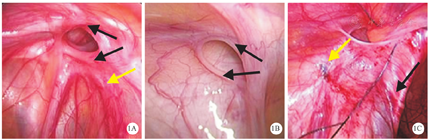

腹腔镜组患儿中,7例术中内环口未发现明显瘢痕,5例可见初次手术结扎线所致的瘢痕,位于腹股沟内环口处(图1A、图1B);6例术中可见输精管未紧贴内环口腹膜(图1C)。复发性腹股沟斜疝患儿腹腔镜内环结扎术术中照片,见图1。

笔者在采用腹腔镜内环结扎术治疗复发性腹股沟斜疝时,有以下几点体会。①打结须紧,必须使用不可吸收线。因为打结位于腹壁外,而线结位于肌层下腹膜外,故线结不容易打紧,而且容易打滑结,若术后腹腔压力增大,则易发生疝复发,因此打结时要保持丝线张力,而且要打方结,最好打2个方结,必要时可采用1-0#丝线或进行双线结扎。本组34例患儿中,5例术中发现内环口瘢痕明显,予以双线结扎。②初次手术疝囊结扎位置较高时,内环口易出现瘢痕,不仅影响疝针潜行,还会因内环口张力增大而影响打结紧度,因此可在瘢痕近端上方进疝针,并沿腹膜外潜行,从而避开瘢痕。③对于输精管的处理:斜疝手术关键是保护好输精管。对于初次手术结扎位置较低,内环口未受干扰而层次清晰者,输精管无黏连而易辨认,可轻松分离绕过。对于初次手术结扎位置较高者,可有2种情况。一种为初次手术结扎疝囊时,已将输精管完全分离开,腹腔镜下可见输精管与内环口有一定距离,反而降低再次腹腔镜手术的难度,本研究腹腔镜组患儿中,6例于术中发现输精管未紧贴内环口腹膜,已有一定距离,就是属于该情况;另一种为输精管仍位于内环口处,并且由于瘢痕明显而不易辨认,该情况进针潜行时无需刻意寻找输精管,只要进针潜行时将腹膜挑起,保证打结时腹膜与丝线之间无输精管,即可避免损伤输精管。④尽量避免多次穿破腹膜或跳跃结扎。⑤若为巨大腹股沟斜疝,可将脐内侧韧带覆盖加强封闭内环口,以降低复发几率[20]。